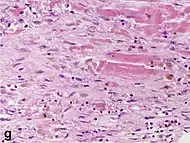

Under the microscope, myocardial infarction presents as a circumscribed area of ischemic, coagulative necrosis (cell death). On gross examination, the infarct is not identifiable within the first 12 hours.[20]

Although earlier changes can be discerned using electron microscopy, one of the earliest changes under a normal microscope are so-called wavy fibers.[21] Subsequently, the myocyte cytoplasm becomes more eosinophilic (pink) and the cells lose their transversal striations, with typical changes and eventually loss of the cell nucleus.[22] The interstitium at the margin of the infarcted area is initially infiltrated with neutrophils, then with lymphocytes and macrophages, who phagocytose ("eat") the myocyte debris. The necrotic area is surrounded and progressively invaded by granulation tissue, which will replace the infarct with a fibrous (collagenous) scar (which are typical steps in wound healing). The interstitial space (the space between cells outside of blood vessels) may be infiltrated with red blood cells.[20]

These features can be recognized in cases where the perfusion was not restored; reperfused infarcts can have other hallmarks, such as contraction band necrosis.[23]

| Myocardial histologic parameters (HE staining)[24] | Earliest manifestation[24] | Full development[24] | Decrease/disappearance[24] | Image |

| Fibroblast and young collagen* | 5–10 days | 2–4 weeks | After 4 weeks; depends on size of infarction; | ![]() |